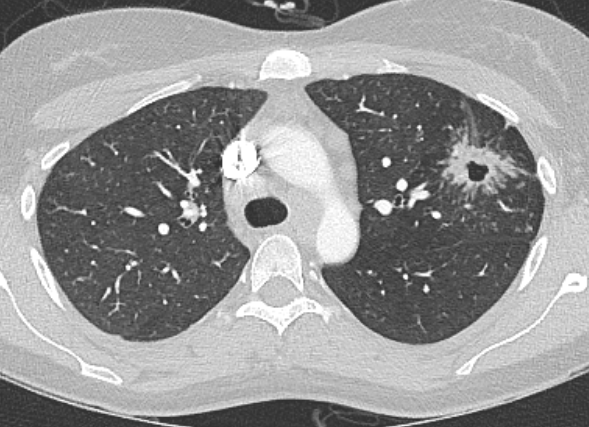

轴位HRCT示左肺上叶可见星系征,中央可见空洞。

本例患者表现为急性多系统结节病,肺部受累伴典型异常,以及左上叶空洞性结节伴“星系征”。

这种类型的结节由众多小尺寸结节汇聚而成,周围环绕着微小的卫星结节,形成独特的“星系征”。

此外,原发性空洞型结节病(PCS)是肺结节病的一种罕见表现形式。